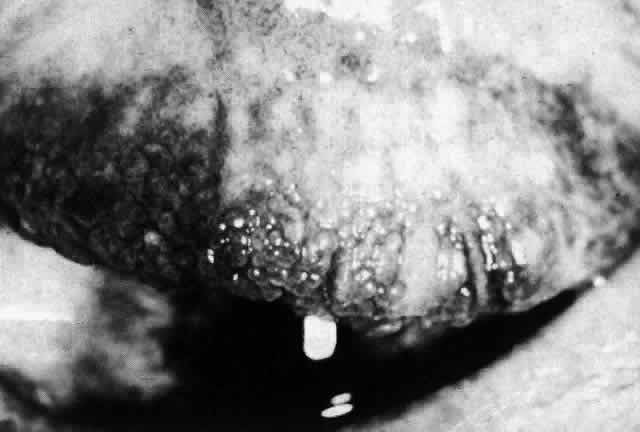

CICATRICIAL PEMPHIGOID

Cicatricial pemphigoid (benign mucous membrane pemphigoid, ocular pemphigoid) is a chronic bullous dermatosis affecting primarily the mucous membranes (Fig. 11). A related bullous dermatosis in which skin lesions rather than mucous membrane lesions predominate is known as bullous pemphigoid. The two diseases have similar histopathologic features and are considered by some observers to represent opposite ends of a single spectrum of disease. In tracing the history of these diseases, one finds that as early as 1794 Wichmann42 reported a case of chronic bullous disease in which the eye was affected and that in 1858 Cooper43 described a patient with blisters of the skin and conjunctiva. Von Graefe44 associated essential shrinkage of the conjunctiva with the end stage of pemphigus, and it was not until 1911 that Thost45 distinguished “cicatricial pemphigoid” from the various forms of pemphigus, a separation that was later emphasized by Civatte46 and Lever47 on the basis of histopathologic studies.

Fig. 11. Cicatricial pemphigoid. Bullous lesions of the oral mucosa. (Courtesy of Dr. HB Ostler)

Cicatricial pemphigoid is often a severe, debilitating, blinding disease. Characterized by symblepharon, obliteration of the fornices (Fig. 12), and corneal ulceration and vascularization, it is one of the most difficult ophthalmologic problems to manage successfully. Severe lid distortion and a dry-eye syndrome may ultimately develop.